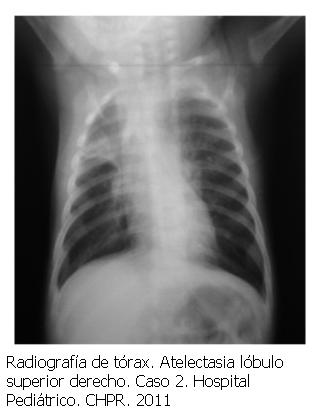

Caso 2. 3 meses, sexo masculino, peso 4.670 g. Recién nacido de término sin patología perinatal. Bronquiolitis con insuficiencia respiratoria, atelectasia de lóbulo superior derecho (figura 3). Antígenos virales positivos para VRS. Recibe tratamiento en sala durante 48 horas con escore de Tal de 7 mantenido, frecuencia respiratoria de 60 rpm, gasometría: pH: 7.285 PCO2: 41 mmHg HCO3 17,2 mEq/L, BE: -7,6 y SatO2 de 99%. Se inicia OAF. A las 2 horas frecuencia respiratoria 51 rpm, escore de Tal 4, gasometría arterial pH: 7,46 PCO2: 39,2 mmHg HCO3 27.3 mEq/l BE: 4,0 SatO2 95%. Al tercer día se realiza fibrobroncoaspiración con resolución de la complicación mecánica. Se mantiene OAF durante 5 días pasando a oxigenoterapia con cánula nasal a 1 l/min. Alta domicilio sin complicaciones